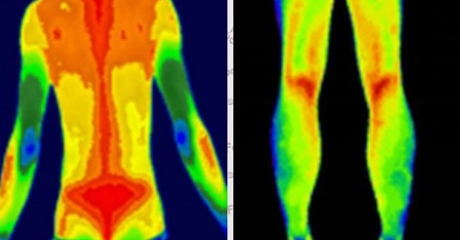

紅外熱成像用于評(píng)估肢體長(zhǎng)度差異【小尺寸紅外機(jī)芯】

漸變運(yùn)動(dòng)中跑步者皮膚溫度變化的紅外熱成像圖

紅外熱成像檢測(cè)神經(jīng)痛【小尺寸紅外機(jī)芯】

紅外熱像儀檢測(cè)訓(xùn)練游泳者肌肉區(qū)域的皮膚溫度變化

紅外熱成像在乳腺疾病的早期檢測(cè)

紅外熱成像在中醫(yī)中的應(yīng)用【小尺寸紅外機(jī)芯】

紅外熱成像對(duì)腰部炎癥的檢測(cè)【手持式紅外熱像儀】

紅外熱像儀應(yīng)用在體育界的重要評(píng)估